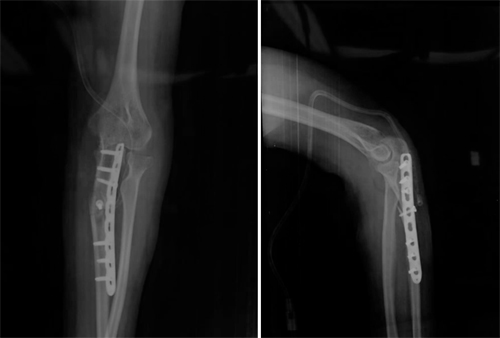

术中体位相显示肘内翻畸形纠正

术后肘关节正侧位X线片显示尺骨畸形矫正,内固定位置良好